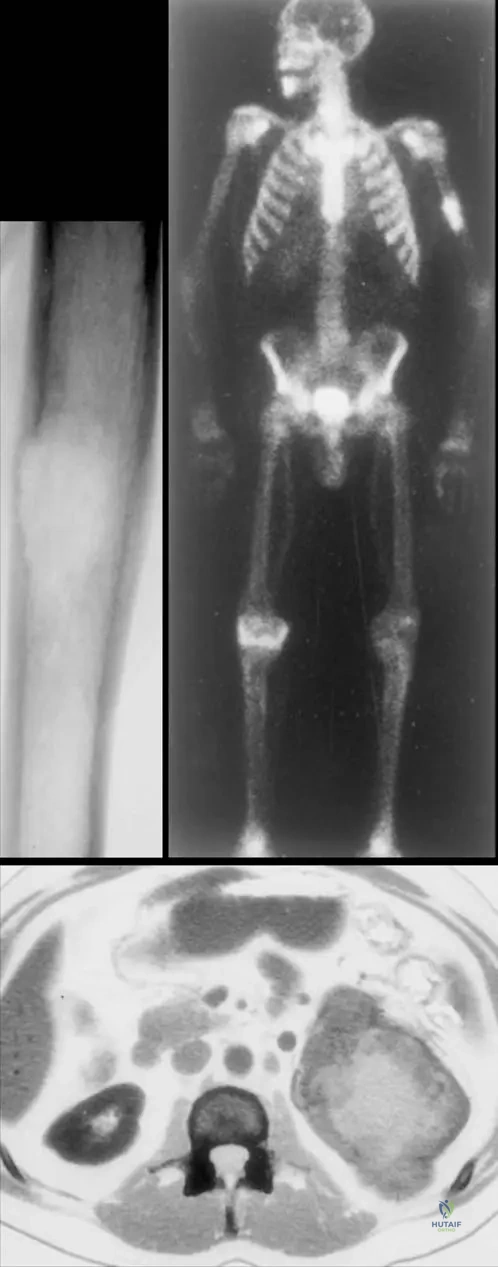

Question 82

View Answer & Explanation

Correct Answer: C

Rationale: The clinical text states, "Patients may present with solitary or multiple lesions, often with a history of cancer. Sometimes, however, a bony metastasis will be the initial presentation of a tumor." This highlights that a new diagnosis of metastatic bone disease can precede the discovery of the primary malignancy. Options A and B are directly contradicted by the text. The image (Fig. 8.122) shows multiple bony metastases, which could be the first sign of an occult primary.

A 70-year-old male with a history of prostate cancer presents with diffuse back pain. A bone scan (Fig. 8.122) shows multiple areas of increased uptake throughout the spine and pelvis. What is the most likely reason for the increased uptake observed on the bone scan?

Rationale: Bone scans (technetium-99m) detect areas of increased bone turnover or osteoblastic activity, where new bone formation is occurring. In the context of metastatic disease, particularly from prostate cancer which is often blastic, the tumor stimulates the surrounding bone to lay down new bone, leading to increased radiotracer uptake. While osteoclastic activity (B) is also involved in bone destruction, the increased uptake on a bone scan primarily reflects the reactive osteoblastic response. Direct visualization of tumor cells (A) is not how bone scans work.

A 68-year-old male presents with new onset, constant, dull pain in his right hip that is worse at night and not relieved by rest. He has a known history of prostate cancer. Radiographs show a sclerotic lesion in the proximal femur. Which of the following imaging modalities would be most appropriate to assess the extent of bony involvement throughout the skeleton?

Correct Answer: D

Rationale: Technetium-99m bone scintigraphy (bone scan) is highly sensitive for detecting osteoblastic activity, making it excellent for screening the entire skeleton for metastatic disease, especially from prostate cancer which often produces blastic lesions. The provided image (Fig. 8.122) demonstrates a bone scan showing multiple bony metastases from prostate carcinoma. While PET-CT is also very sensitive, bone scintigraphy is a more traditional and often initial screening tool for widespread bony involvement. MRI is excellent for local staging and soft tissue involvement but not for whole-body screening in this context. Plain radiographs are less sensitive for early lesions.